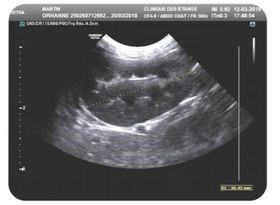

La Polykystose Rénale (PKD)

C'est une maladie héréditaire qui touche plusieurs races de chat dont le Maine Coon. Cette maladie affecte les reins et induit la présence de kystes remplis de liquide. La taille de ces cavités va augmenter avec l’âge et envahir peu à peu le rein jusqu’à ce que le tissu rénal ne soit plus assez important pour assurer ses fonctions d’épuration du rein. Le chat atteint commencera alors à présenter des symptômes qui au départ sont peu discernables comme la polydipsie (augmentation de la prise de boisson) et polyurie (augmentation du volume des urines). Si l’insuffisance rénale progresse davantage, le chat s'alimente de moins en moins, perte de poids, nausées éventuelles. Il peut également avoir du sang dans ses urines.

Cette insuffisance chronique rénale est irréversible.

Cette maladie peut être diagnostiquée soit par la réalisation de test ADN, soit par échographie.

Toutefois certains chats homozygotes sains (non porteur du gène muté) pourront développer une PKD non liée à la mutation du gène PKD1. Il est donc recommandé de réaliser des échographies rénales qui recherchent la présence clinique de Kystes quelque soit leurs origines.